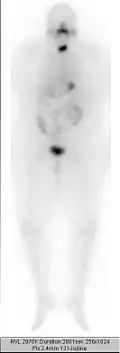

Radiothérapie d'un cancer de la thyroïde à l'iode 131 (dose : 3,7 GBq), 1re phase.

Seconde phase (zones foncées = zones de concentration).